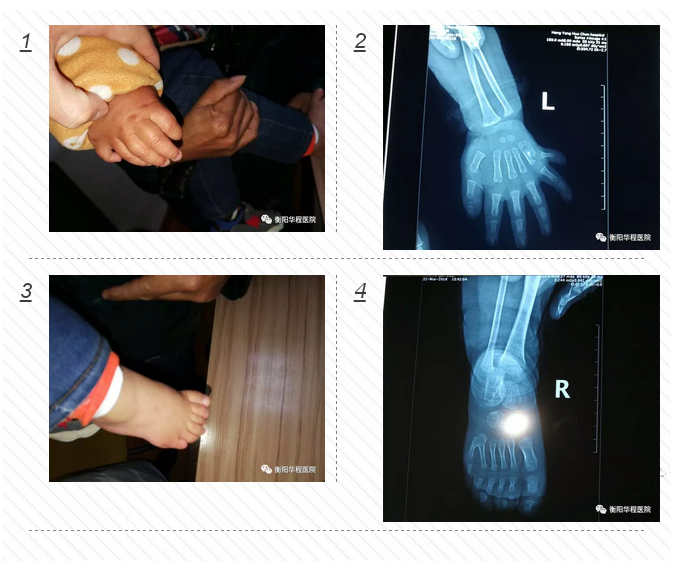

正常人一般只有兩個(gè)大拇指,可家住衡陽縣集兵鎮(zhèn)的1歲大的城城,雙手和雙腳比常人各多出1個(gè)小手指和1個(gè)小腳趾,不過在衡陽華程醫(yī)院骨科中心醫(yī)護(hù)人員的幫助下,3月23日下午,多出來的手指和腳趾已被成功切除。

面對(duì)這位只有1歲的小患者,骨科中心醫(yī)護(hù)人員進(jìn)行了一番細(xì)致檢查。尹治華醫(yī)生發(fā)現(xiàn)小城城的“多指”情況并不是特別復(fù)雜,突出的關(guān)節(jié)部位并沒有長出骨頭,只需切除多出的指頭,再將表皮重新縫合,扎死血管和神經(jīng)就可以了。“孩子太過幼小,血管和神經(jīng)均很纖細(xì),需借助顯微成像技術(shù)完成手術(shù)。而留下的疤痕組織也會(huì)在成長過程中逐漸減淡。”骨科中心尹治華醫(yī)生表示。3月23日小城城在全麻下行雙側(cè)多指、多趾切除功能重建術(shù),經(jīng)過一個(gè)小多小時(shí)的焦急等待,孩子平安從手術(shù)室里出來了,手術(shù)非常成功,小城城媽媽那顆懸著的心終于著了地。